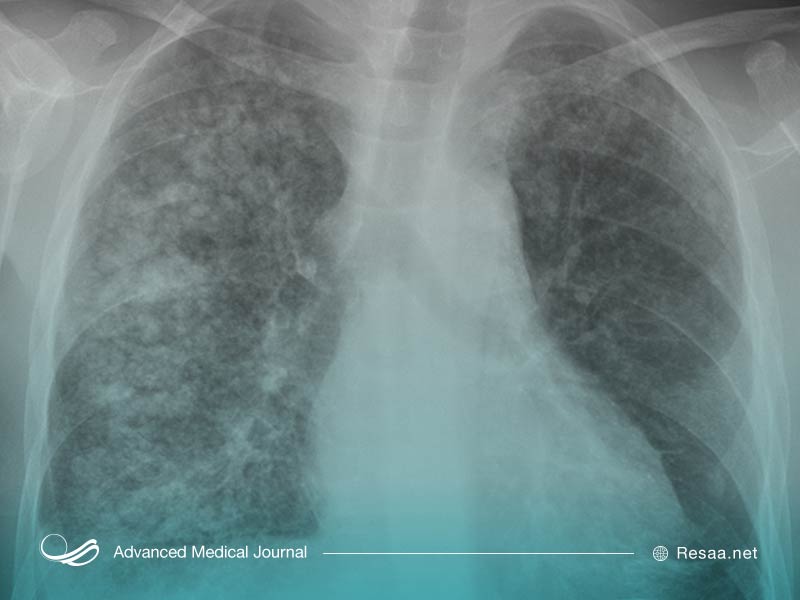

کلسیفیکاسیون پستان

فقط یک ماموگرافی میتواند کلسیفیکاسیون پستان را تشخیص دهد.

پزشکان کلسیفیکاسیون پستان را بر اساس اندازه رسوب کلسیم طبقهبندی میکنند.

کلسیفیکاسیون ماکرو، رسوبات بزرگ و کاملاً مشخصی هستند. این موارد معمولاً نشانه سرطان نیستند.

از طرف دیگر میکروکلسیفیکاسیونها “Microcalcifications” به صورت لکههای کوچک در اشعه ایکس و از طریق ماموگرافی ظاهر میشوند. این موارد نیز معمولاً جای نگرانی ندارند اما وجود رسوباتی با اشکال و اندازههای مختلف که در ناحیهای از سلولهای به سرعت در حال تکثیر جمع شدهاند، ممکن است نشانه سرطان باشد.